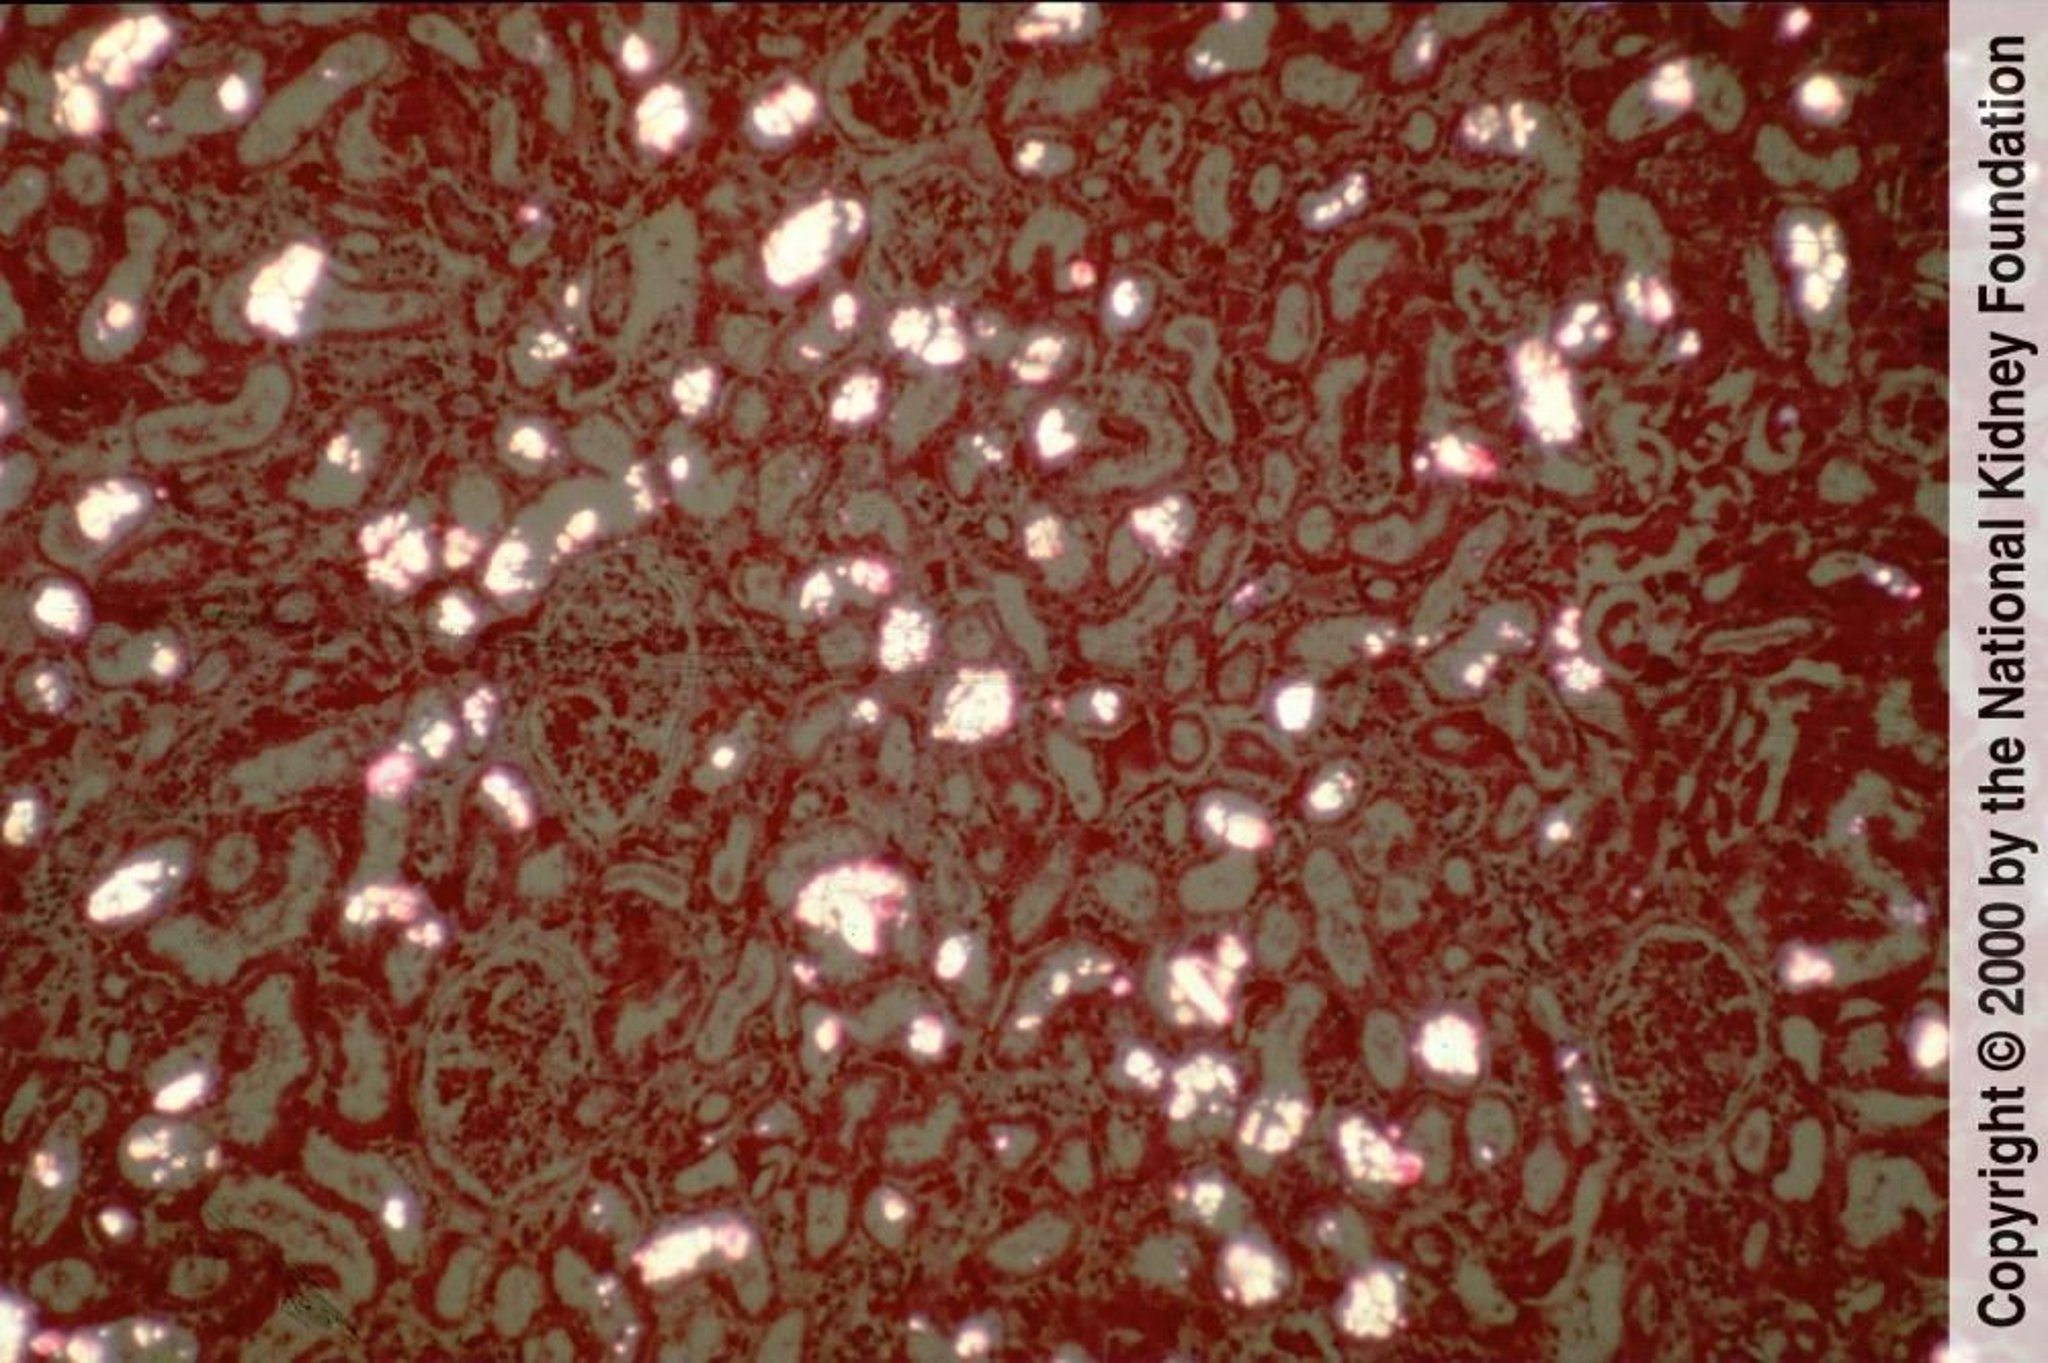

Hiperoxaluria

Los cristales de oxalato de calcio precipitan en los túbulos renales y son fácilmente visibles como cristales birrefringentes y en forma de abanico o de pila de hojas capa bajo luz polarizada (tinción de hematoxilina-eosina con luz polarizada, ×100).

Image provided by Agnes Fogo, MD, and the American Journal of Kidney Diseases' Atlas of Renal Pathology (véase www.ajkd.org).